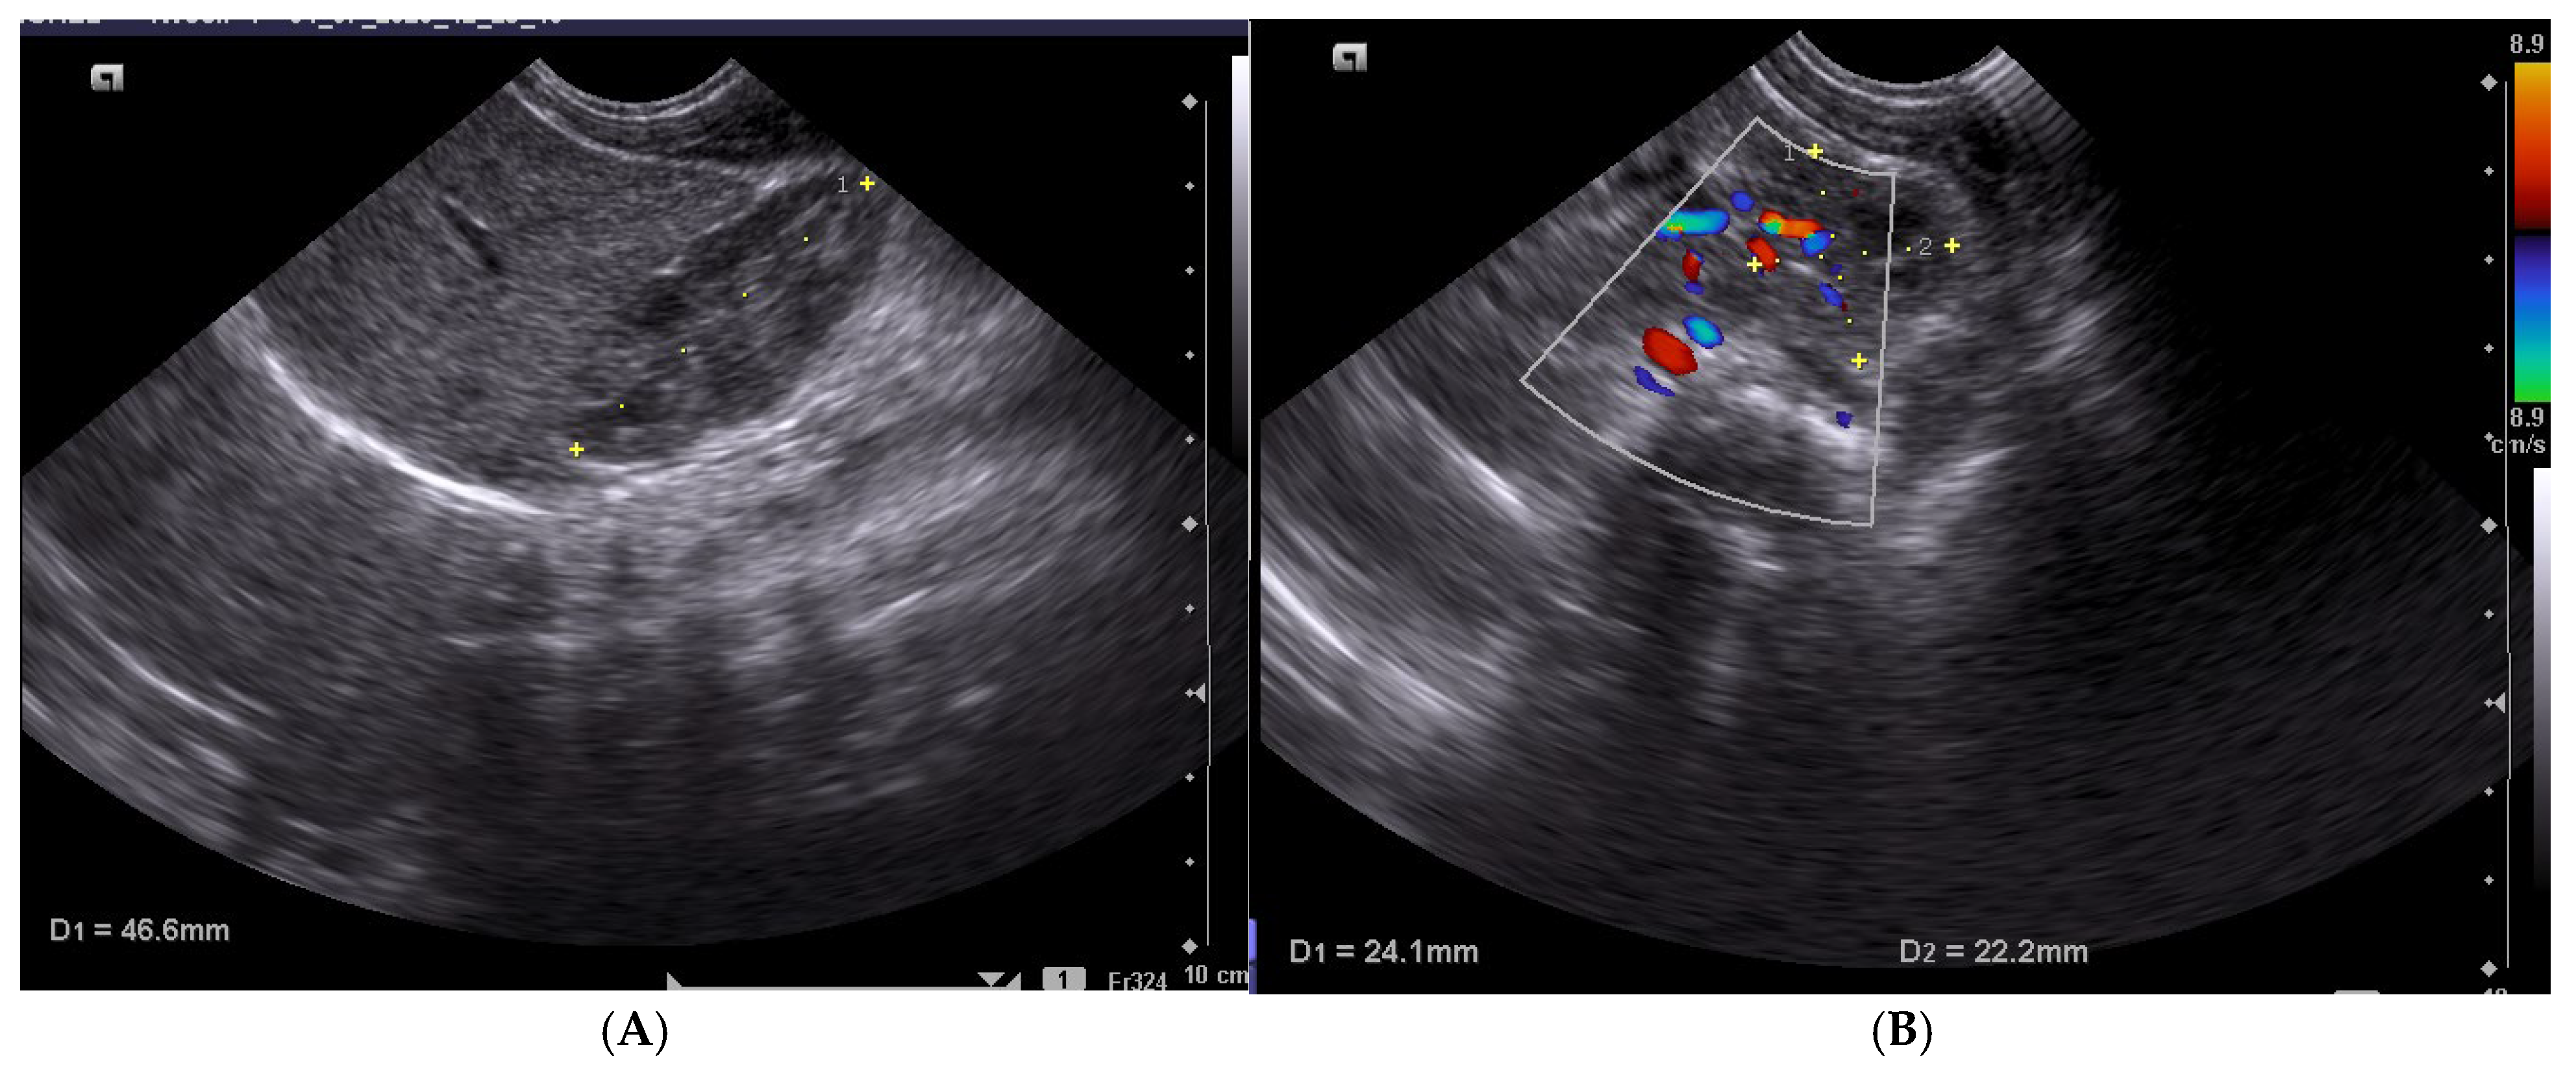

2.3. Ultrasound Methodology